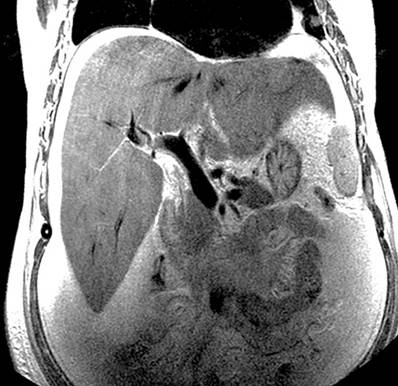

Por lo anterior, se decidió realizar una angiografía venosa por resonancia magnética, la cual evidenció el adelgazamiento de la vena suprahepática derecha con un calibre irregularmente adelgazado de hasta 3 mm, compatible con una probable trombosis y ausencia del vacío de la señal proximal a la VCI, trayectos adelgazados y filiformes de la vena suprahepática izquierda y la porción proximal de la vena suprahepática media, lo que sugiere una probable trombosis parcial; la vena porta con calibre de 13 mm, sin signos de trombosis. El informe radiológico de la angiografía venosa por resonancia magnética encontró la vena porta con un trayecto conservado y un afinamiento de las venas suprahepáticas, lo que sugiere un probable síndrome de Budd-Chiari (Figuras 1 y 2).

Figura 1 Afinamiento de las venas suprahepáticas (MRI). Fuente: Servicio de Radiología, Hospital Víctor Lazarte Echegaray.

Figura 2 Afinamiento de las venas suprahepáticas y vena porta de calibre conservado (MRI). Fuente: Servicio de Radiología, Hospital Víctor Lazarte Echegaray.